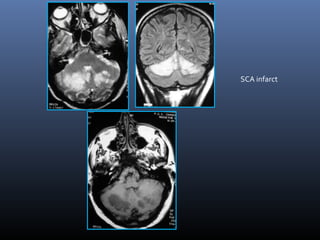

SCA infarct